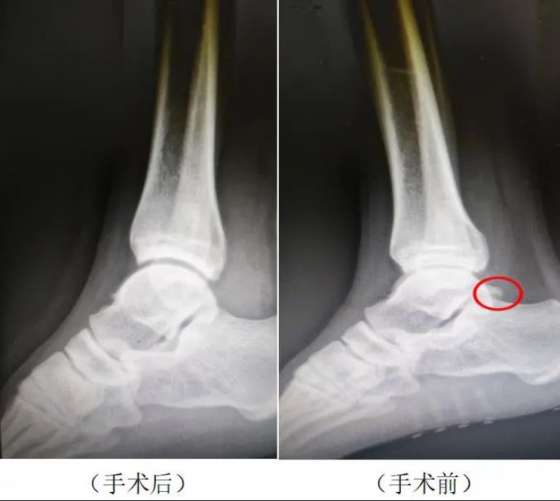

大约8个月前,国安队球员闫雨开始出现右足跟后方疼痛、踝关节跖屈位加重,无法正常发力起跳,经过休息肿胀有所缓解,但运动后依然疼痛,反反复复,导致无法完成日常训练。为了彻底解决这一健康问题,北京国安决定由德尔康尼为闫雨进行诊断和治疗。经影像学检查,闫雨被初步诊断为右踝关节撞击综合症、右跟距关节后方骨赘形成、右侧跟腱炎。

11月14日,北京德尔康尼骨科医院副主任医师邢朝辉医生为闫雨实施了关节镜下右踝关节撞击综合症、跟距关节后方骨赘切除手术。手术非常成功,闫雨目前恢复良好,他表示德尔康尼长期为国家队高水平运动员进行医疗保障服务的宝贵经验和良好的业内声誉让他对手术和康复充满信心,他也期待不久的将来就能回到赛场继续为球队贡献自己的力量。